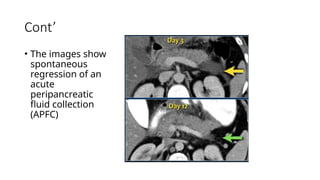

Cont’

• The images show

spontaneous

regression of an

acute

peripancreatic

fluid collection

(APFC)